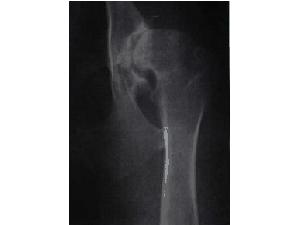

DKK - dysplazie kyčelních kloubů

Vývojová vada postihující hlavně velké rasy psů. Kloub a kloubní jamka do sebe přesně nezapadají, nebo nejsou dostatečně vyvinuty.

Označování: pravá/levá<br />

0 (A) - bez vady<br />

1 (B) - přechod mezi bezvadným a lehkou DKK<br />

2 (C) - lehká DKK<br />

3 (D) - střední DKK<br />

4 (E) - těžká DKK

Kategorie: Veterina, nemoci